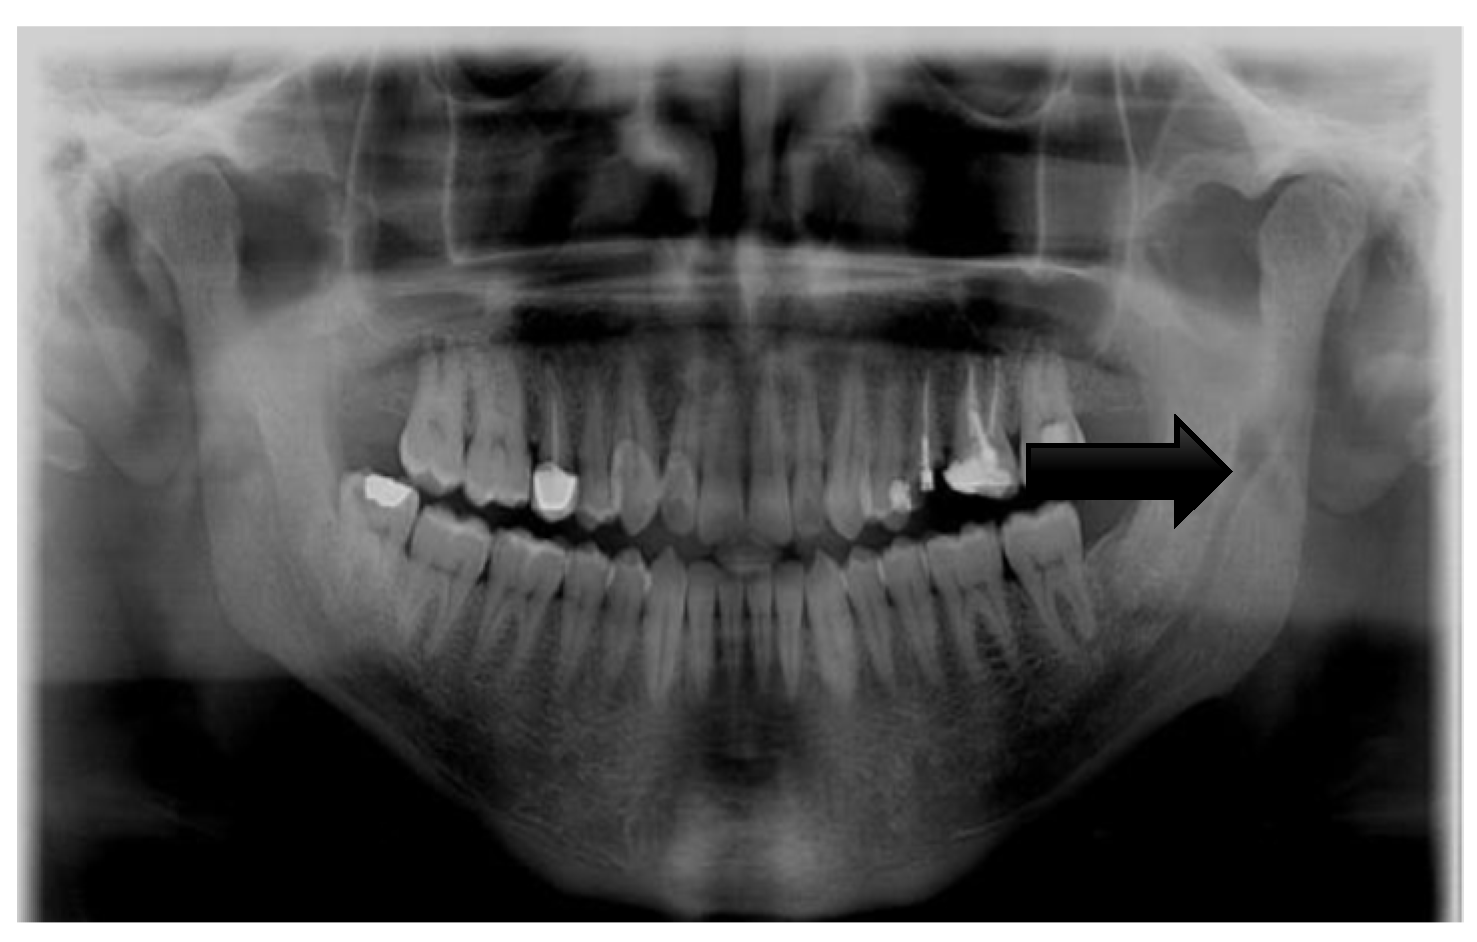

| Input image | Panoramic Radiograph | 2D Panoramic Radiograph images |